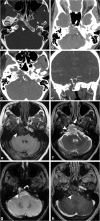

Calvarial lesions are often asymptomatic and are usually discovered incidentally during computed tomography or magnetic resonance imaging of the brain. Calvarial lesions can be benign or malignant. Although the majority of skull lesions are benign, it is important to be familiar with their imaging characteristics and to recognise those with malignant features where more aggressive management is needed. Clinical information such as the age of the patient, as well as the patient's history is fundamental in making the correct diagnosis. In this article, we will review the imaging features of both common and uncommon calvarial lesions, as well as mimics of these lesions found in clinical practice. TEACHING POINTS: • Skull lesions are usually discovered incidentally; they can be benign or malignant. • Metastases are the most frequent cause of skull lesions. • Metastatic lesions are most commonly due to breast cancer in adults and neuroblastoma in children. • Multiple myeloma presents as the classic "punched out" lytic lesions on radiographs. • Eosinophilic granuloma is an osteolytic lesion with bevelled edges.